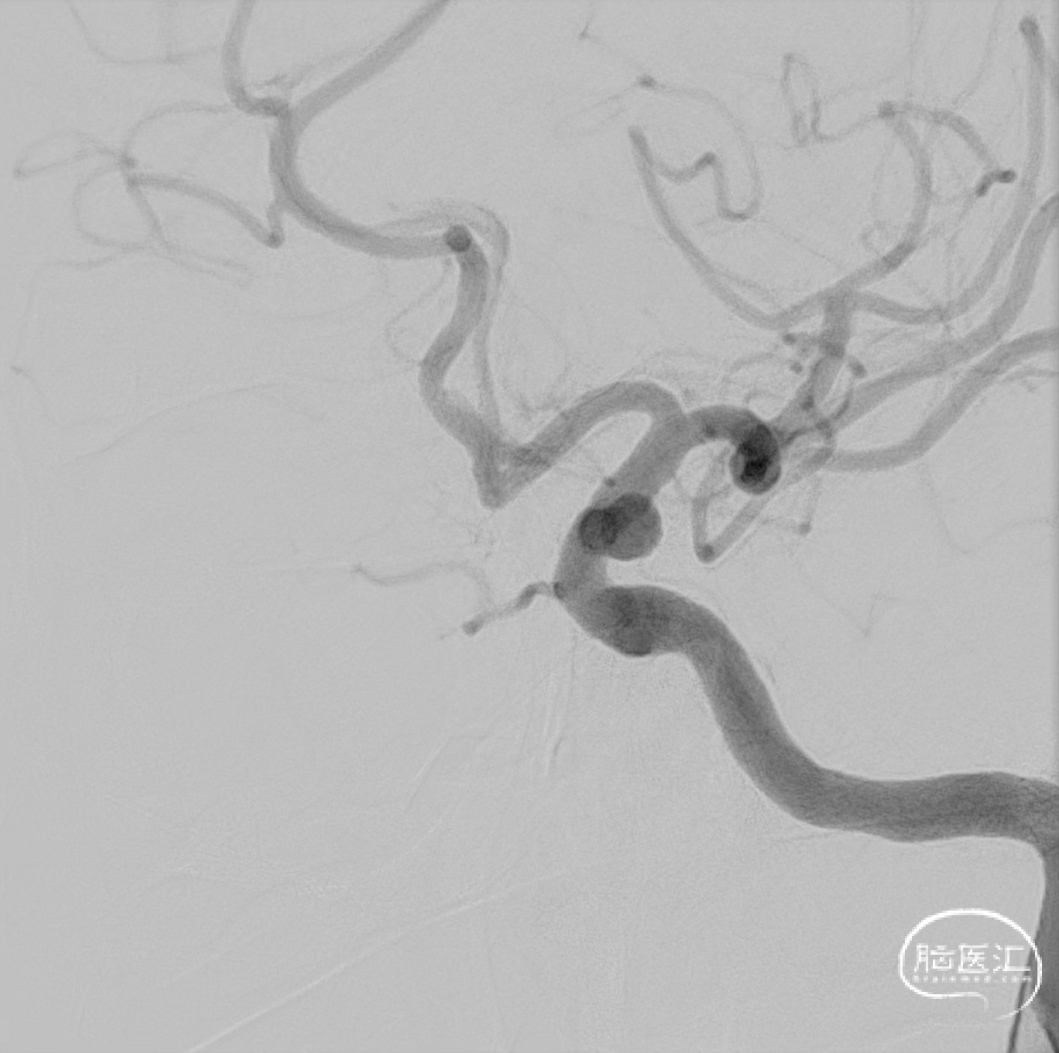

术前DSA造影:

左侧颈内动脉眼动脉段动脉瘤。

左侧颈内动脉眼动脉段动脉瘤:动脉瘤约为6.21*5.11mm(H*W),瘤颈宽约为4.72mm。

载瘤动脉近端锚定点直径:4.72mm

载瘤动脉远端锚定点直径:3.54mm